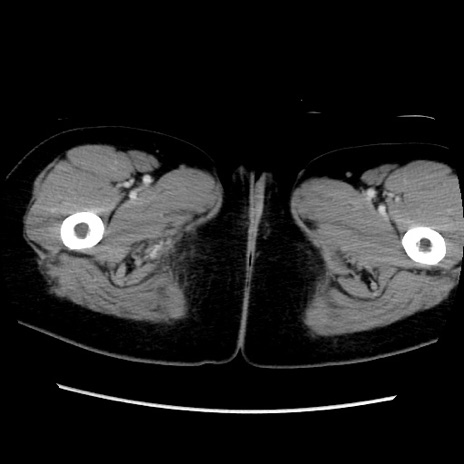

MRI(4日後)

【症例】40歳代女性

【主訴】上下腹部痛

【現病歴】2日目から下腹部痛あり。夜間は痛みで眠れなかった。昨日より上腹部痛と下痢が出現。臥位で痛みは軽快したため、休んでいた。本日になって臥位でも立位でも痛みが強くなってきたため救急要請。

【既往歴】子宮内膜症

【身体所見】部:平坦・軟、左上下腹部に圧痛あり、反跳痛あり。

【データ】WBC 21800、CRP 26.78